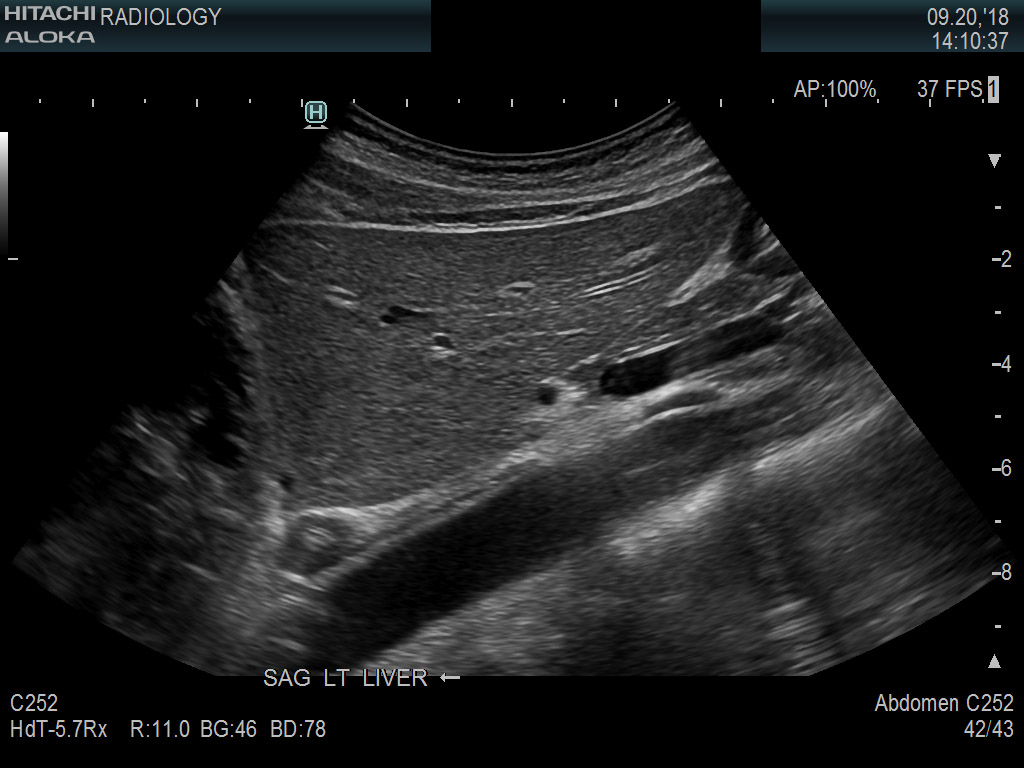

Superior guidance for all applications

Fujifilm Healthcare Americas is committed to designing tools that help surgeons navigate inside the human body and provide the necessary information to immediately make critical surgical decisions.

Fujifilm Healthcare's dedication to Surgeons provides outstanding ultrasound technology, professional support and the specialized tools necessary to best perform comprehensive real-time ultrasound imaging in Breast Surgery, General Surgery, Laparoscopic Surgery, Neurosurgery, Robotic Surgery and Surgical Oncology.

Learn moreArietta 65

The Arietta 65 has many advanced and unique probes that fully cover the expanding range of procedures that benefit from ultrasound guidance.

Learn moreArietta 65

The Arietta 65 has many advanced and unique probes that fully cover the expanding range of procedures that benefit from ultrasound guidance.